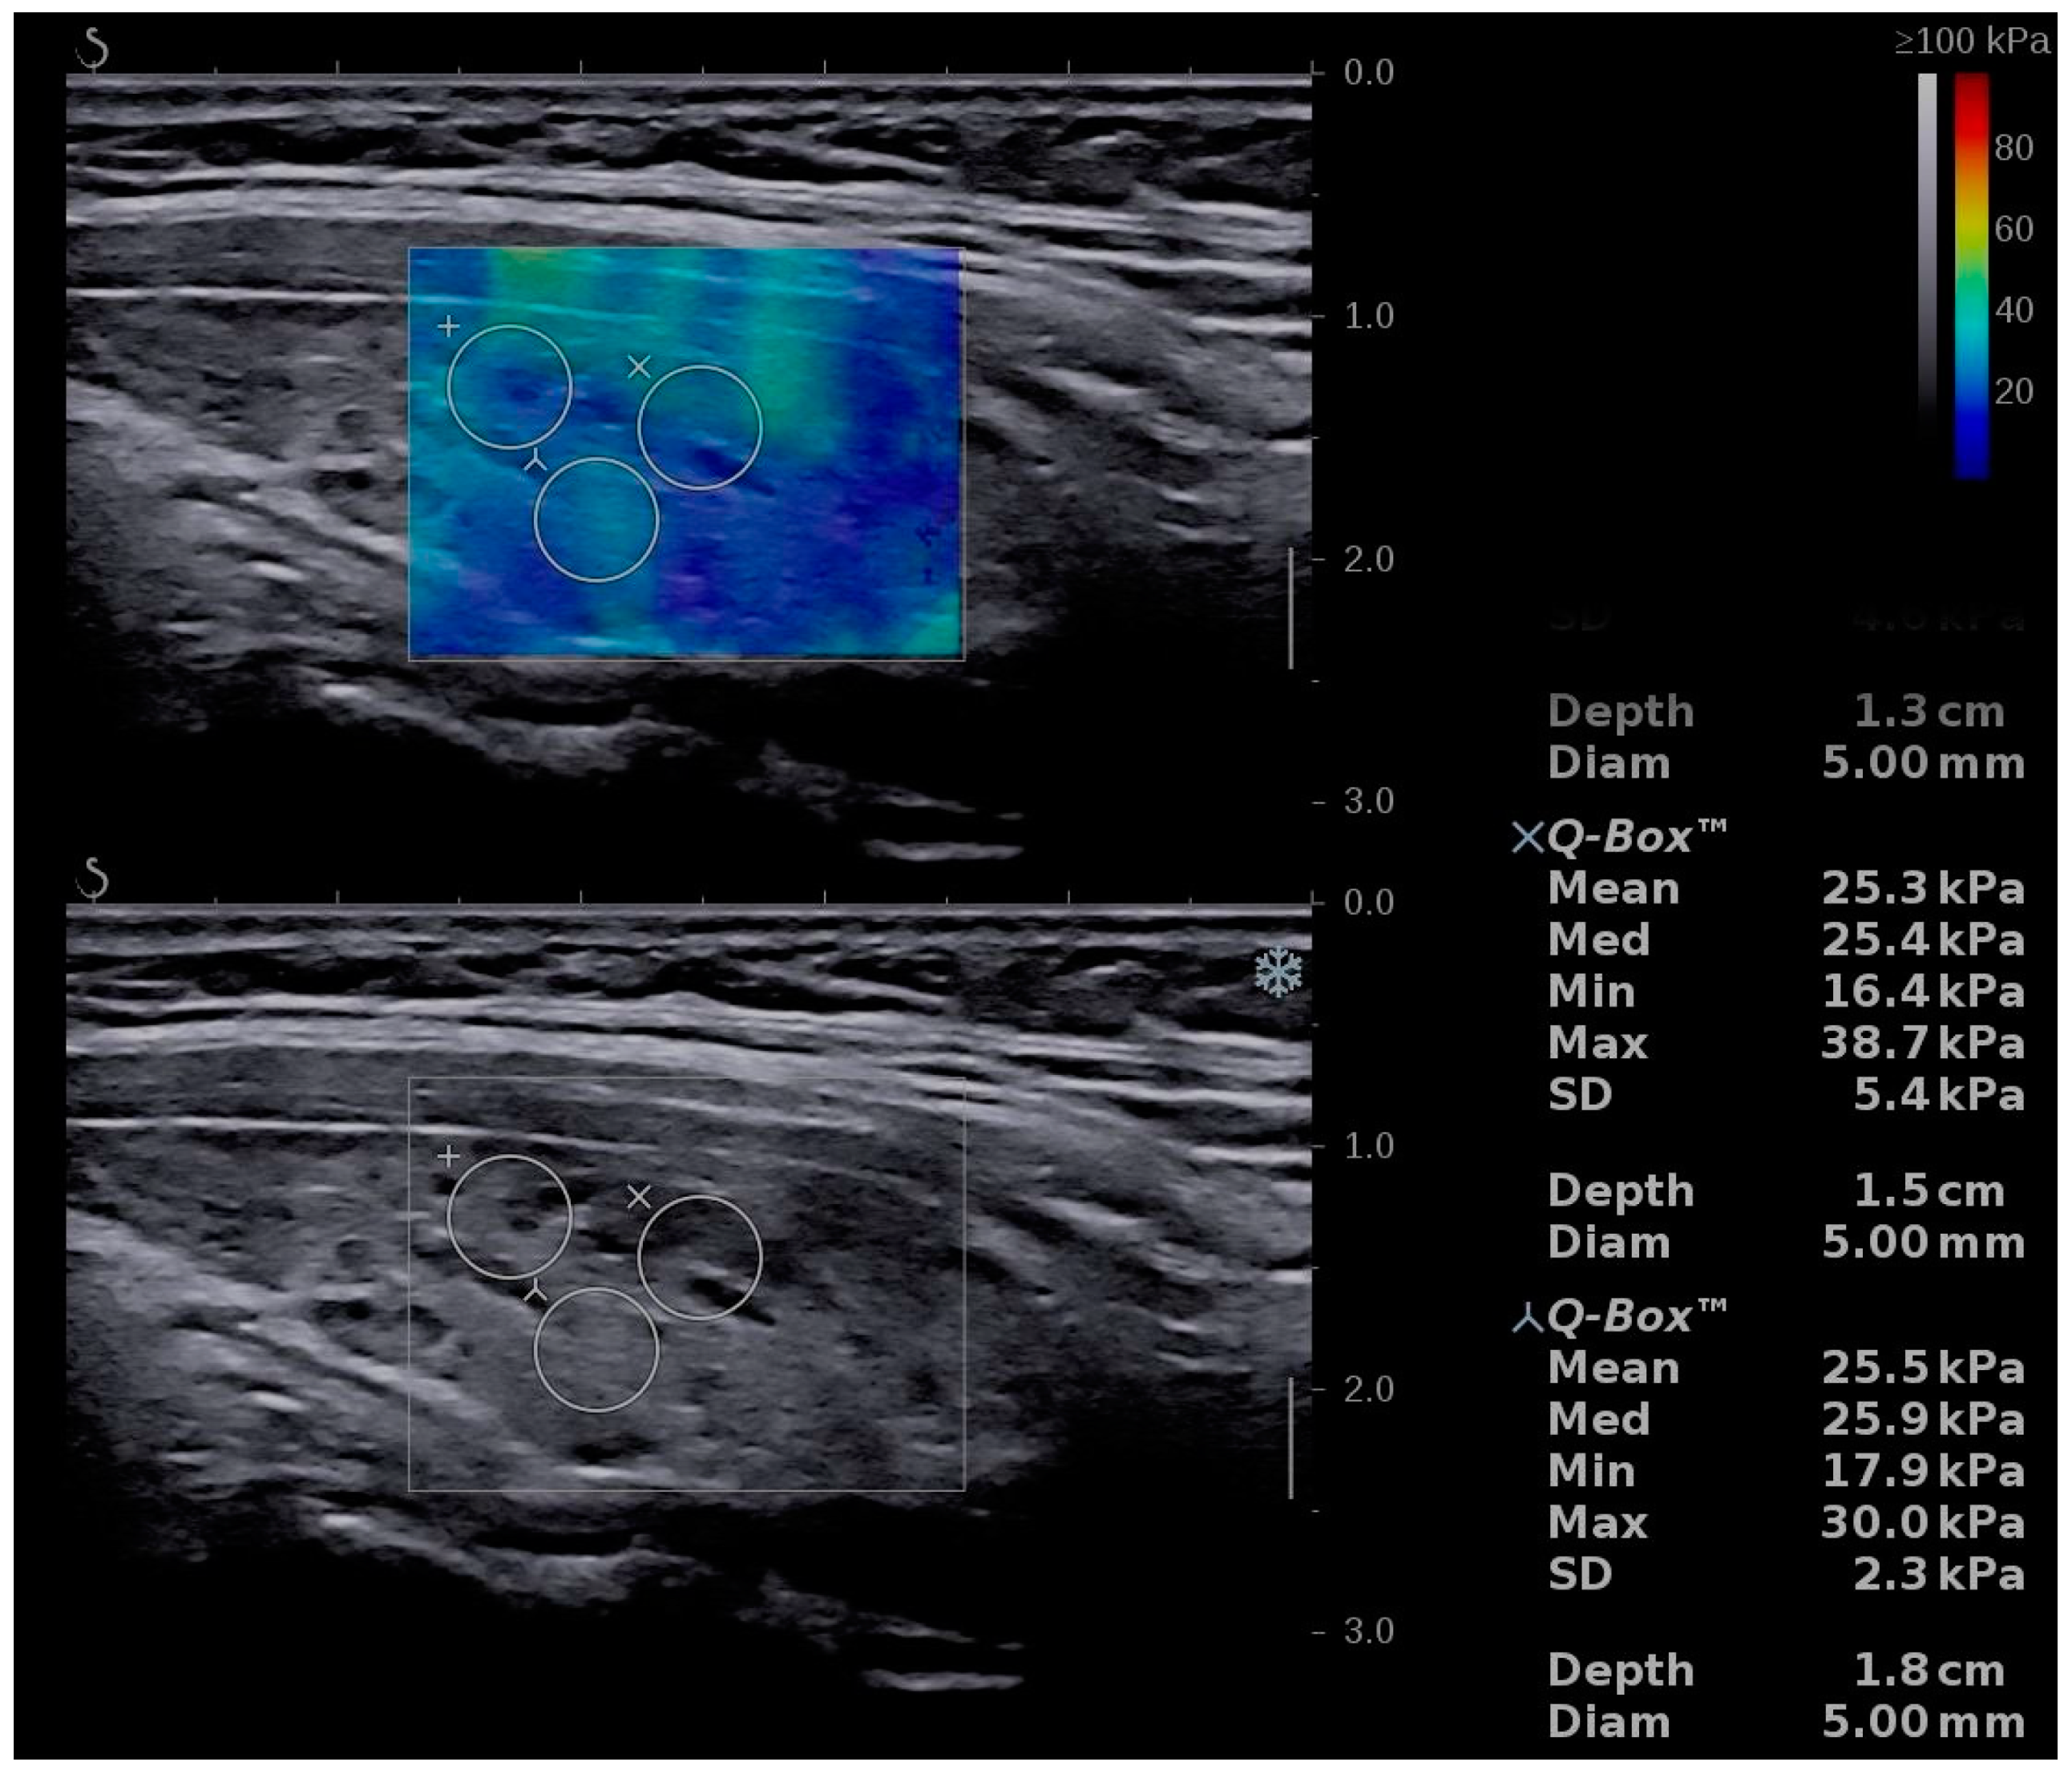

2.5. Conventional Ultrasound and Elastography Examination